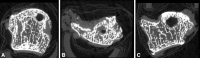

Methods: We addressed the morphology, load, and movement of the human thumb, emphasizing the CMC joint in normal and arthritic states. We present comparative anatomy, gross dissections, microscopic analysis, multimodal imaging, and live-subject kinematic studies to support or challenge the current understanding of the thumb CMC joint and its predisposition to disease.

Results: The current evidence suggests structural differences and loading characteristics predispose the thumb CMC to joint degeneration, especially related to volar or central wear. The patterns of degeneration, however, are not consistently identified, suggesting influences beyond inherent anatomy, repetitive load, and abnormal motion.